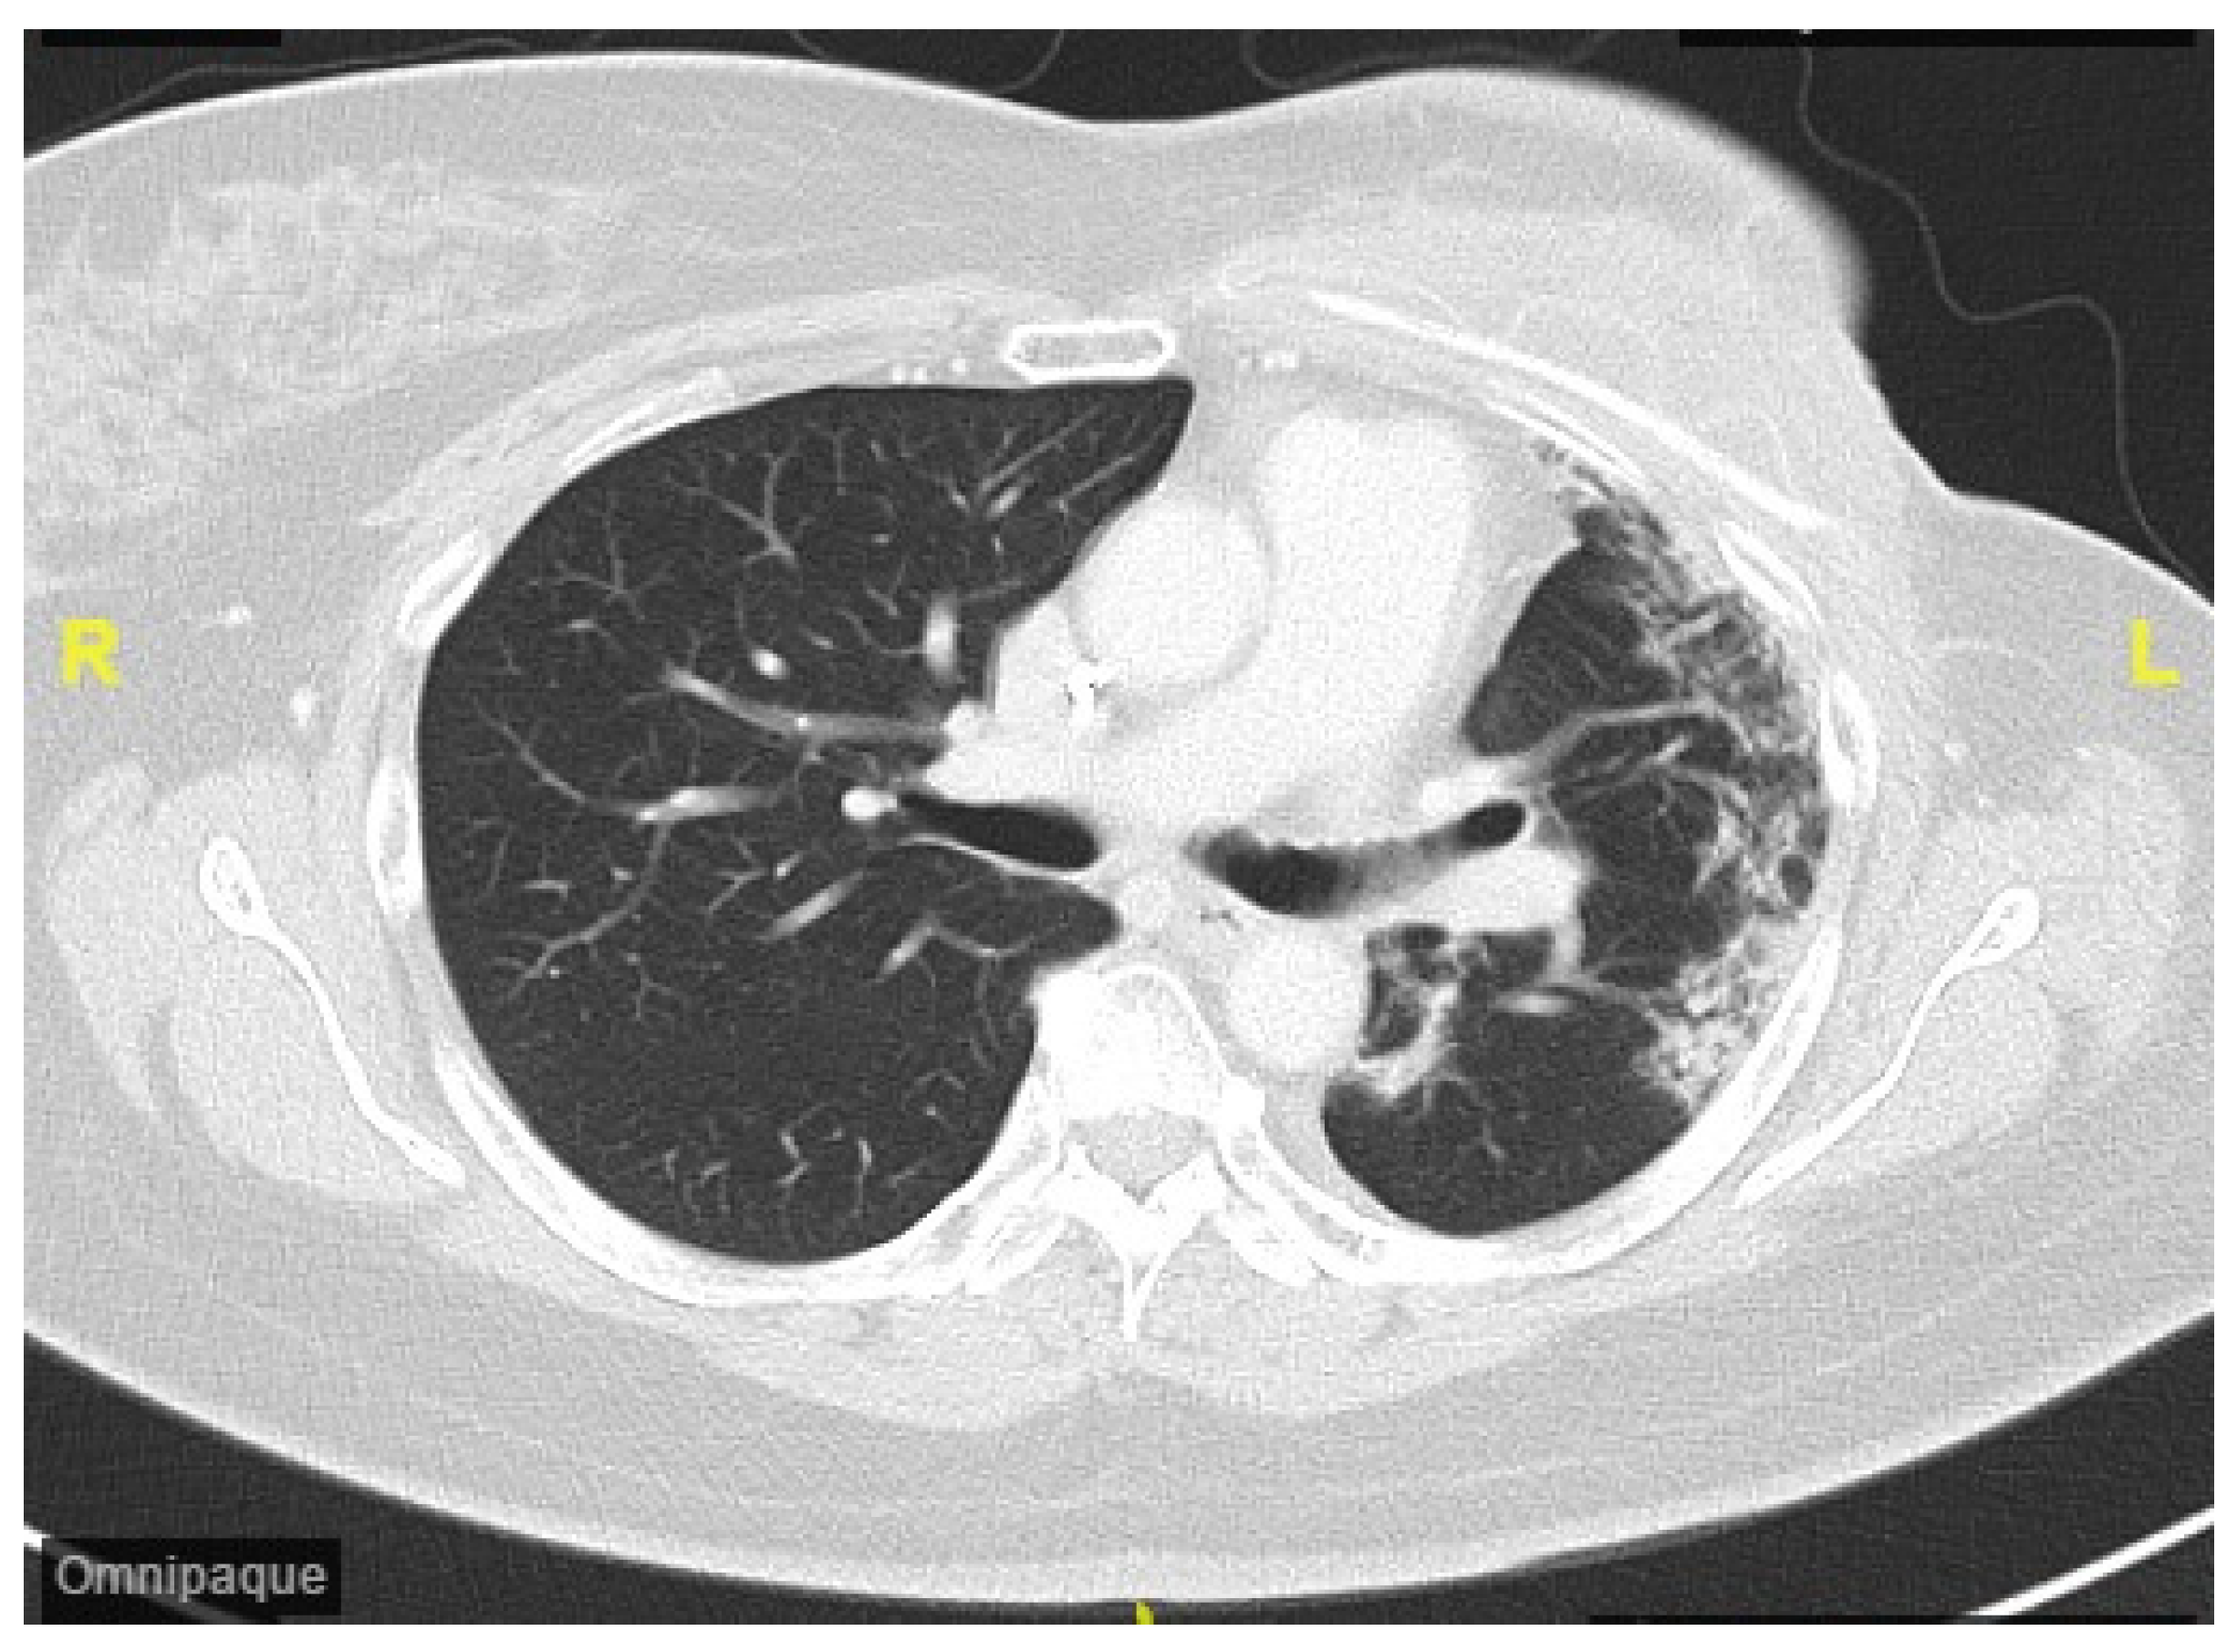

3. Case